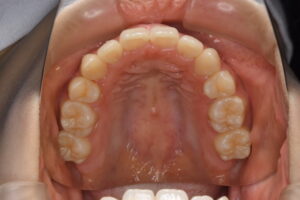

実際の症例紹介(20代女性/裏側ワイヤー矯正)

治療前

治療後

・主訴:八重歯と前歯の突出

・治療法:裏側からのワイヤー矯正(リンガル)

・治療期間:約1年半〜2年(目安)

・予想される副作用・リスク:装置装着後の違和感・疼痛、発音のしづらさ、一時的な咀嚼効率低下、ブラッシング不良によるむし歯・歯周病リスク など

※写真は代表的な症例です。口腔内の状態により治療法や期間は異なります。詳細は初診相談でご説明します。